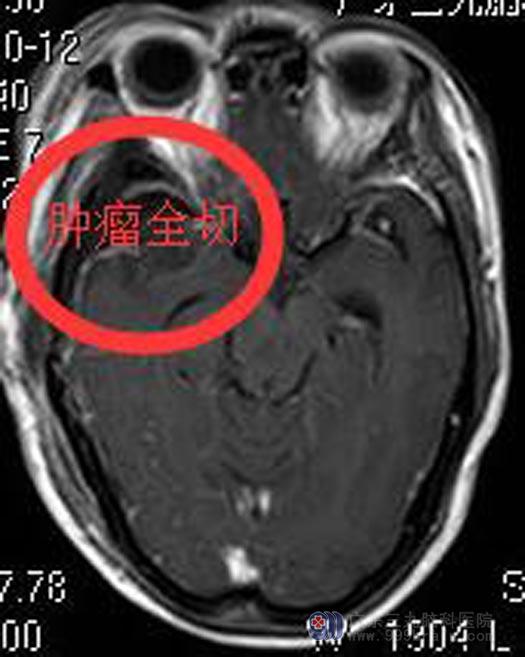

9. 手术简要:术中显微镜下见灰白色肿瘤部分裸露,肿瘤质韧,有完整包膜,血供较丰富,仔细分离出颈内动脉、大脑中动脉、大脑前动脉及视神经,全部切除肿瘤,对颈内动脉、大脑中动脉、大脑前动脉、视神经、动眼神经保护完整。

10. 术后恢复好,症状消失,神志清醒,遵嘱活动。

11. 术后MRI:肿瘤完全切除。

12. 术后病理:脑膜瘤,WHOⅠ级。